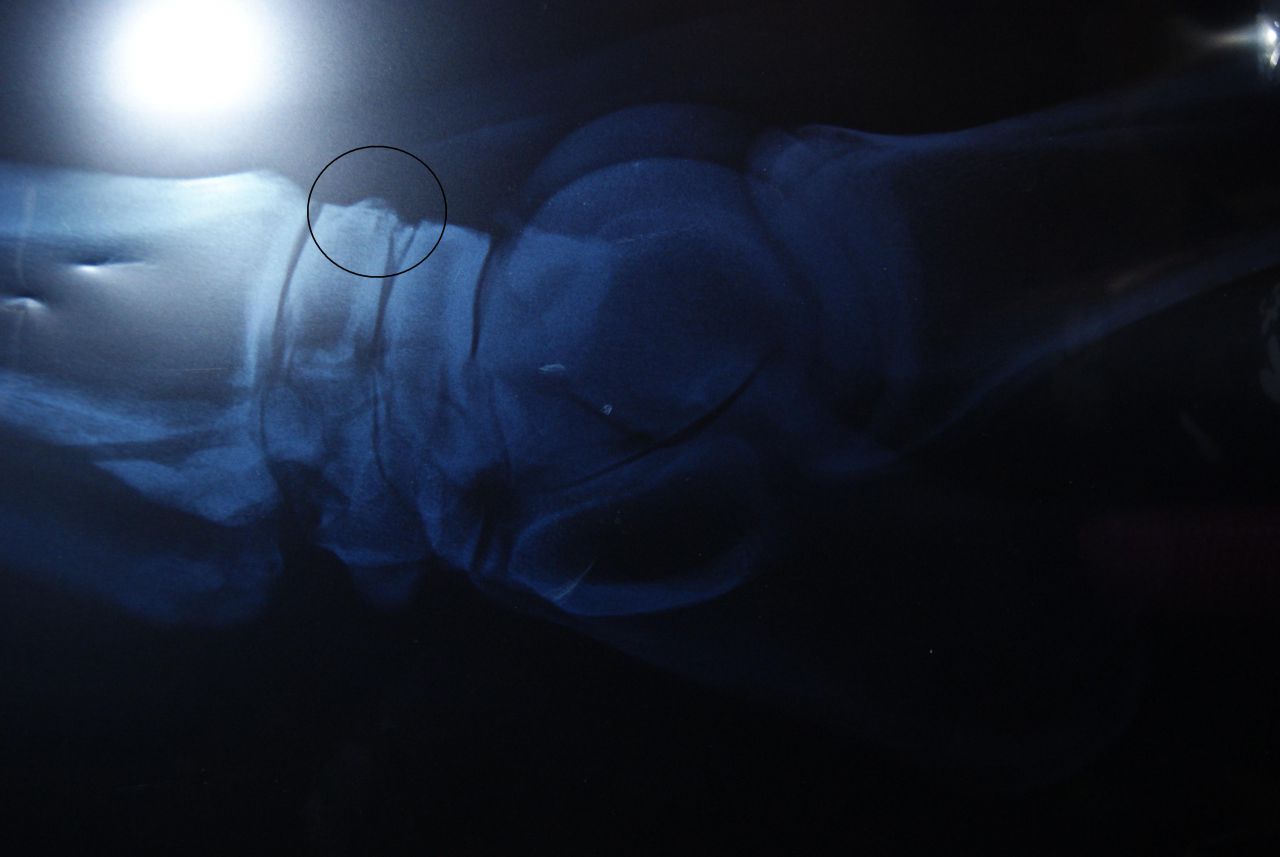

Déconnecté | Je viens enfin de récupérer les 3ième radios de mon cheval qui souffre d'un éparvin Le véto m'a montré ou c'était (j'ai fais des ronds pour vous montrer) mais apparement, il n'y aurait pas que ce que je montre dans le cercle, l'éparvin se voit aussi à un autre endroit. Quelqu'un sait me le dire ? Première radio à 4 ans [url=https://www.1cheval.com/membre/services/photos/images/137389.jpg] ![]() [/url] deuxième radio en avril 2012 [url=https://www.1cheval.com/membre/services/photos/images/137390.jpg] ![]() [/url] Et troisième radio fin septembre qui montre une évolution postive (éparvin en cours de solidification après avoir reçu du Tildren en juin) [url=https://www.1cheval.com/membre/services/photos/images/145646.jpg] ![]() [/url] Je crois qu'il y a une histoire de tassement des étages osseux ? On le voit bien sur la troisième radio... Bref aux profs des radios pouvant m'éclairer encore et encore ! Merci |